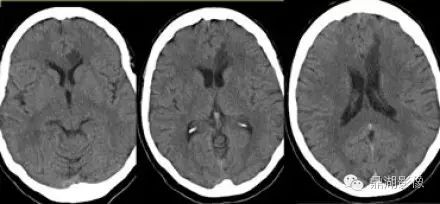

分水岭梗塞(外分水岭和内分水岭)

ce41b2b33f038df087e0d5b30c3599e4.jpg